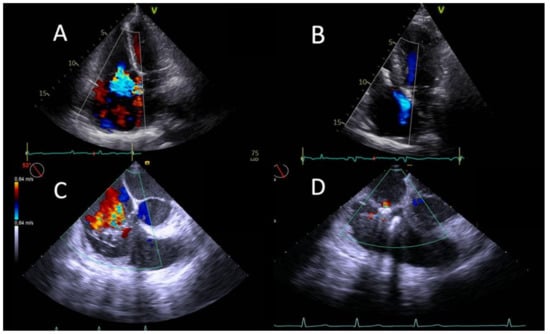

3.2. Procedural and Echocardiographic Results